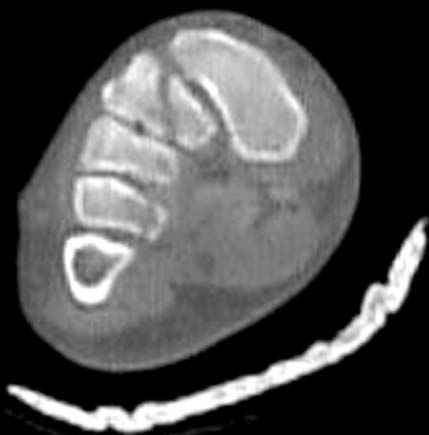

Здесь КТ и сравнительные снимки стопы под нагрузкой.

Диагностировано повреждение медиальной и латеральной колонны.

Если оперативное лечение - как и каким доступом?